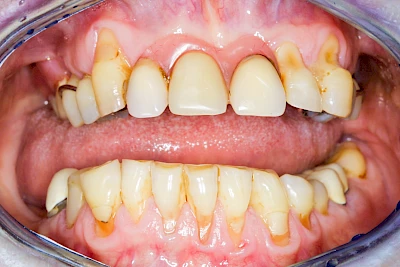

Bakterien in den Zahnbelägen greifen neben den Zähnen auch das Zahnfleisch (Gingiva) und den gesamten Zahnhalteapparat (Parodont) an. Der Körper reagiert mit einer Entzündung, sichtbar als Rötung und Schwellung. Meist blutet das Zahnfleisch z .B. beim Essen oder auch beim Putzen der Zähne.

Ist zunächst nur das Zahnfleisch von der Entzündung betroffen, spricht man von Gingivitis. Später, wenn auch der Knochen um die Zähne herum entzündet ist, spricht man von einer Parodontitis. Bei der Parodontitis wird der Knochen nach und nach abgebaut und das Zahnfleisch zieht sich zurück. Die Zahnhälse und Zahnwurzeloberflächen liegen mehr und mehr frei. Die Zähne werden zunehmend lockerer und fallen schließlich aus.